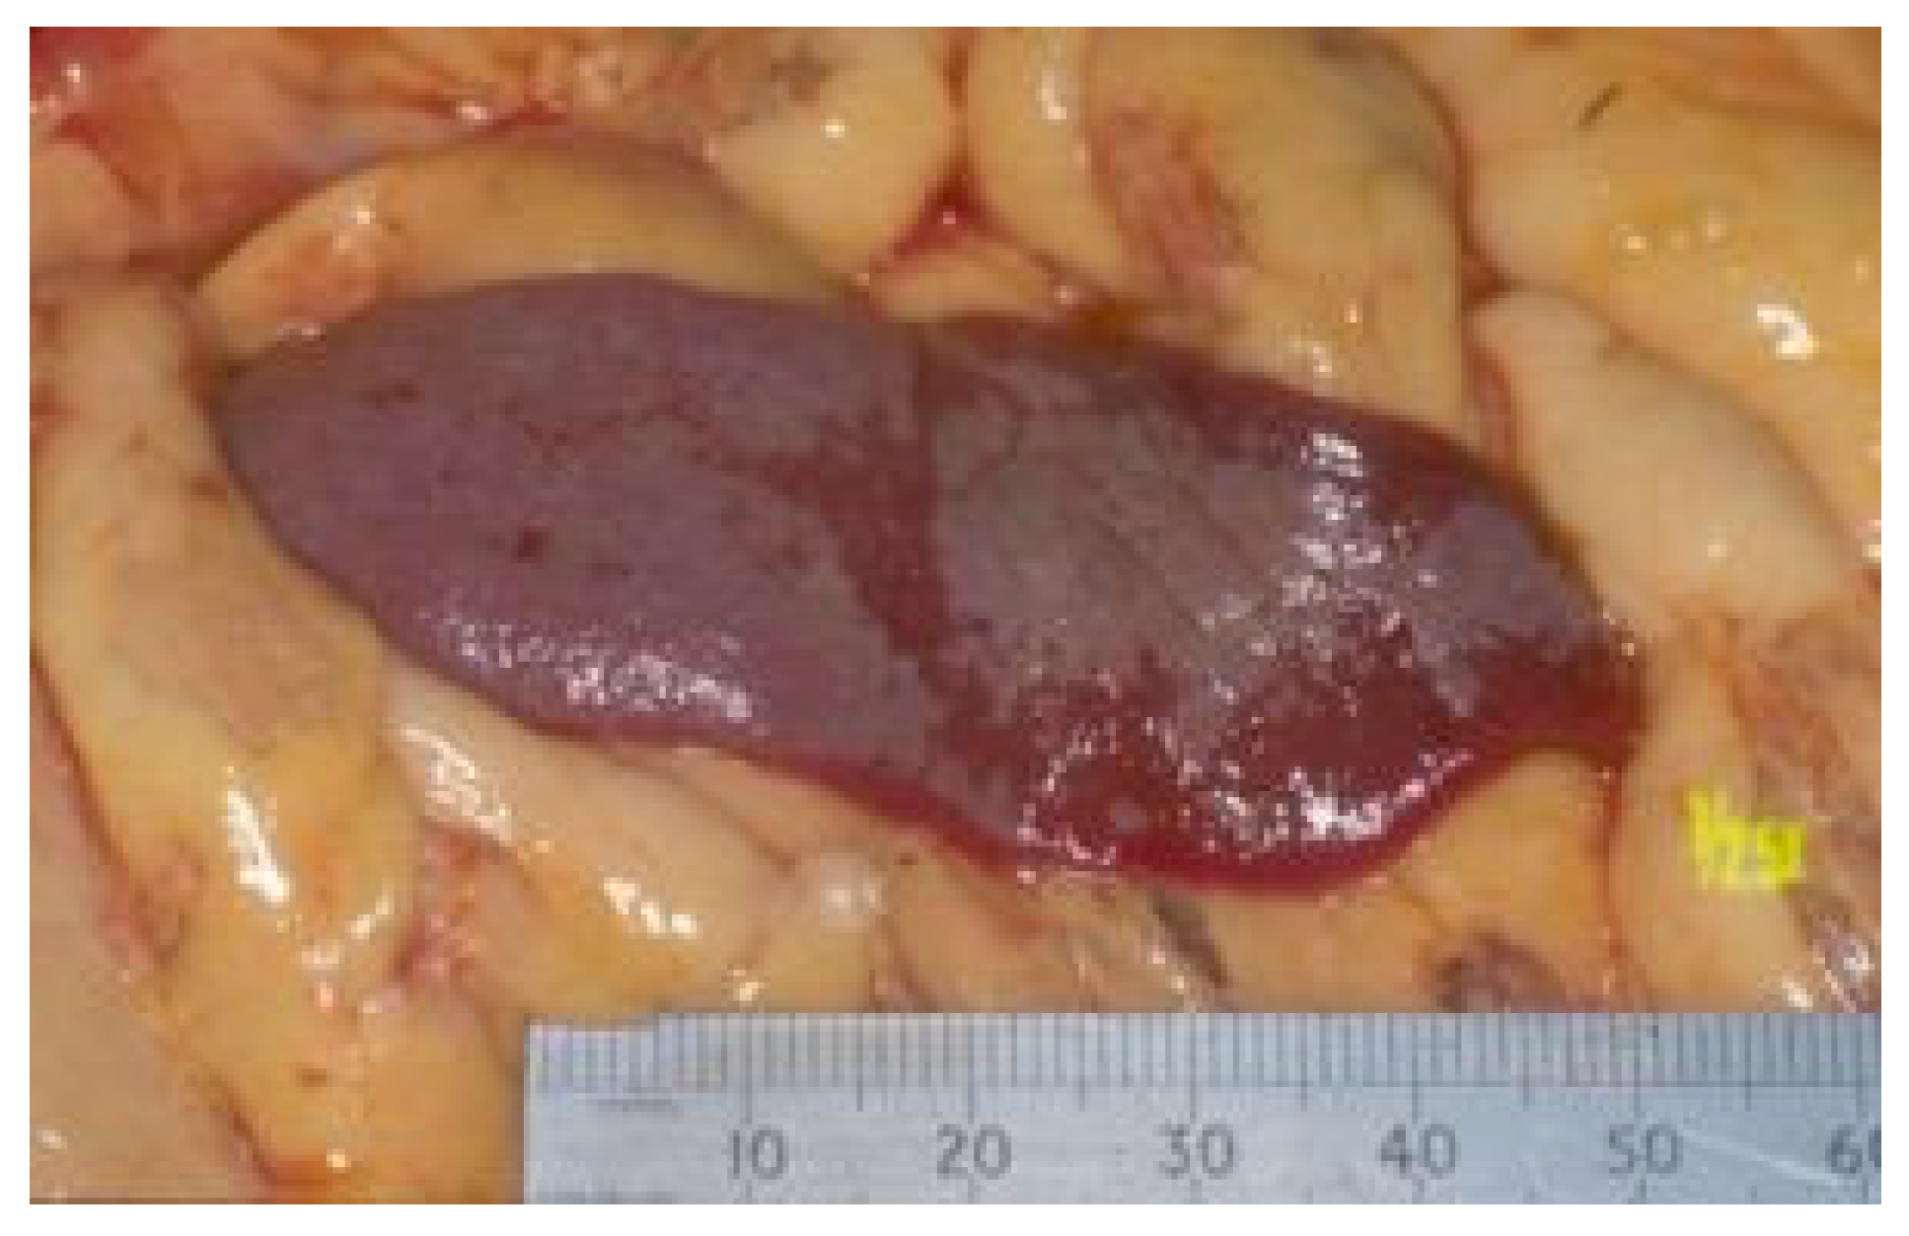

7.4. Diagnostic Imaging in FIP

7.4.1. Routine Imaging: Ultrasonographic and Radiographic Findings

| Summary of Section 7: Diagnosis of FIP; Section 7.4: Diagnostic imaging in FIP: No specific ultrasonographic or radiographic findings exist for FIP. Ultrasonography (in particular) and radiography can show the presence of effusions. Pneumonia due to FIP that is occasionally reported can be associated with radiographic changes. Ultrasonography can reveal abdominal lymphadenomegaly or lymphadenopathy and/or abnormalities of the liver, spleen, intestines and/or kidneys (which can include a medullary rim sign), depending on which organs are affected. Imaging can also be of use to the direct sampling of abnormal tissues, e.g., fine-needle aspirate for cytology examination to reveal non-septic pyogranulomatous inflammation, or ultrasound-guided needle core (e.g., tru-cut) biopsies can be collected and submitted for histopathology. When a cat is showing neurological signs, the imaging of the brain by magnetic resonance imaging, if available, with contrast, can be useful to demonstrate neurological abnormalities (such as obstructive hydrocephalus, syringomyelia, foramen magnum herniation and marked contrast enhancement of the meninges, third ventricle, mesencephalic aqueduct, and brainstem). A description of computerised tomography findings in cats with neurological FIP has not been published, but MRI is likely to be more sensitive in the detection of subtle intraparenchymal lesions. Advanced imaging of the central nervous system is indicated before performing cerebrospinal fluid sampling to assess the potential risk of herniation. |